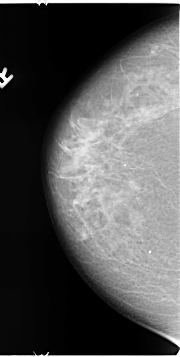

B_3123_1.LEFT_MLO

LEFT_CC LINES 4680 PIXELS_PER_LINE 2288 BITS_PER_PIXEL 12 RESOLUTION 50 OVERLAY

LEFT_MLO LINES 4696 PIXELS_PER_LINE 2680 BITS_PER_PIXEL 12 RESOLUTION 50 OVERLAY

FILE: B_3123_1.LEFT_CC.OVERLAY

TOTAL_ABNORMALITIES 1

ABNORMALITY 1

LESION_TYPE MASS SHAPE ARCHITECTURAL_DISTORTION MARGINS ILL_DEFINED

ASSESSMENT 4

SUBTLETY 3

PATHOLOGY BENIGN

TOTAL_OUTLINES 1

BOUNDARY